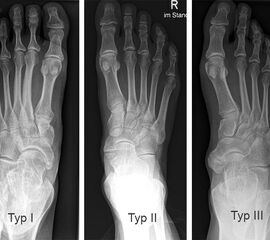

Radiologische Einteilung (Abb. 2)2:

Typ I: Ovalär bis rundliches, glatt begrenzter akzessorischer Knochen im Sehnenansatz des musculus tibialis posterior liegt.

Typ II: Trianguläres Ossikel, welches eine knorpelige Verbendung (Synchondrose) zum Os navicularis pedis hat. Typ II ist die häufigste Variante 2.

Typ III: Nach medial erweitertes Os naviculare im Sinne eines Os naviculare cornutum (entspricht einem fusioniertem Typ II).